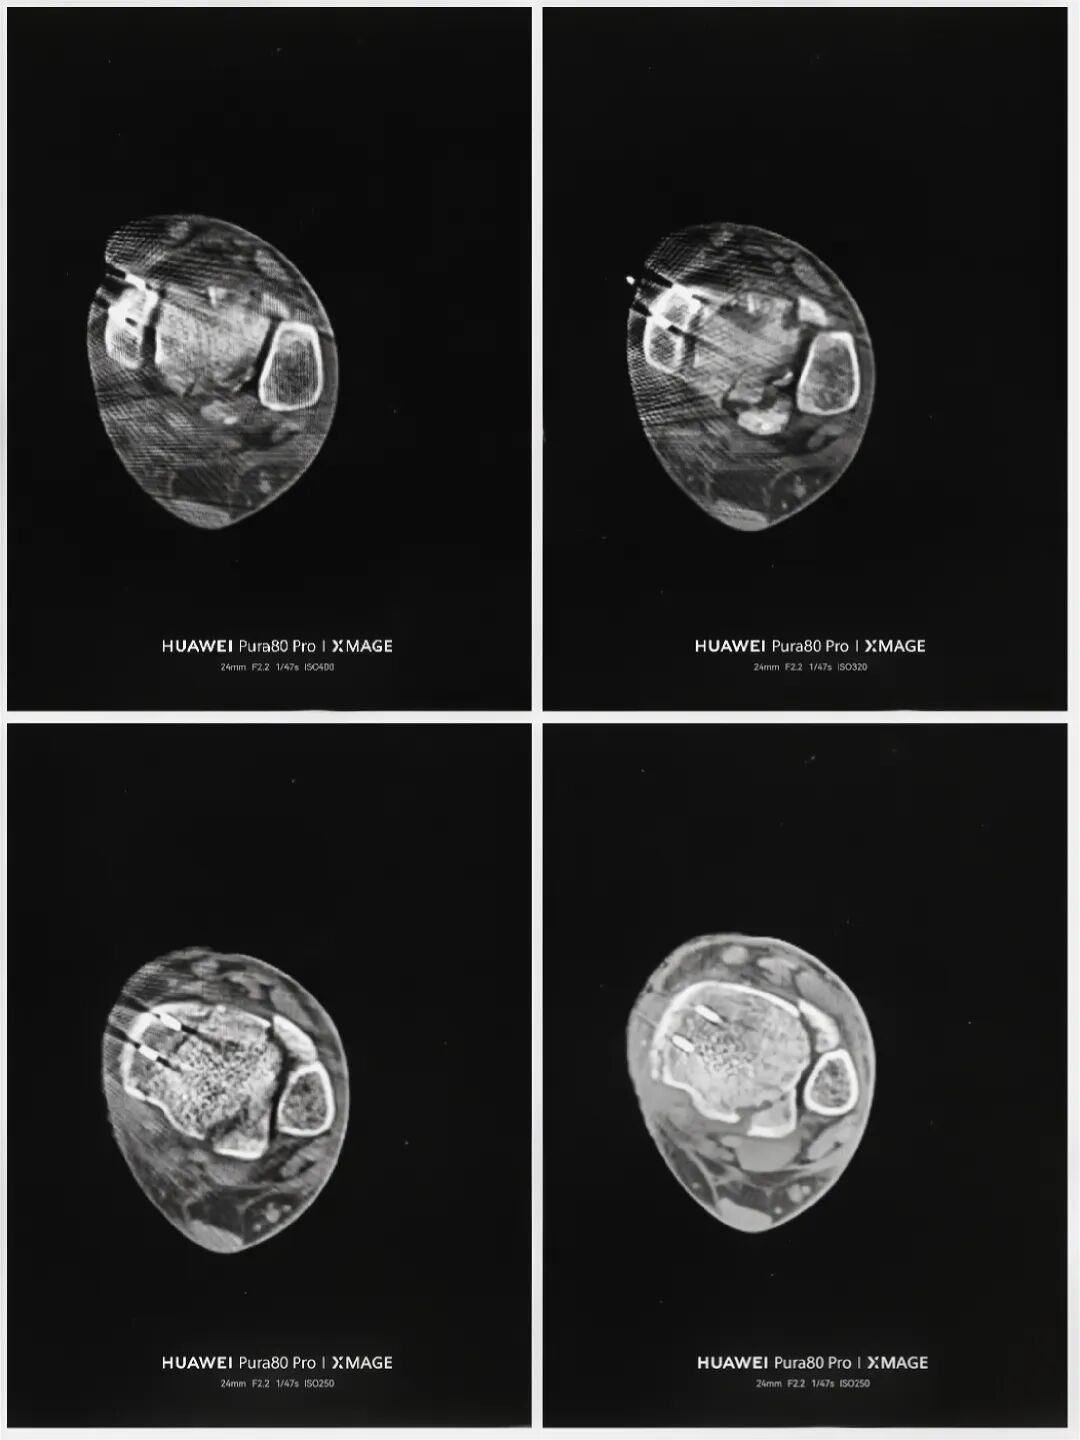

术后复查:

图片